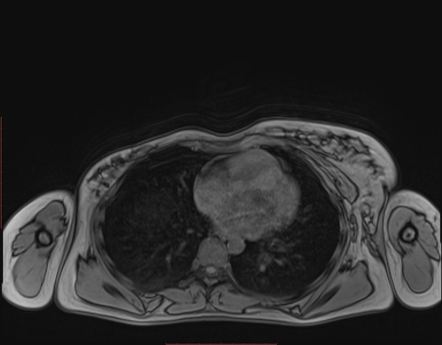

Poland Syndrome | Image | Radiopaedia.org

radiopaedia.orgLiving With Poland Syndrome. How To Live With Poland Syndrome?

radiopaedia.orgLiving With Poland Syndrome. How To Live With Poland Syndrome?

Poland Syndrome | Radiology Case | Radiopaedia.org

radiopaedia.orgPoland Syndrome Causes, Symptoms, Diagnosis, Treatment & Prognosis

radiopaedia.orgPoland Syndrome Causes, Symptoms, Diagnosis, Treatment & Prognosis